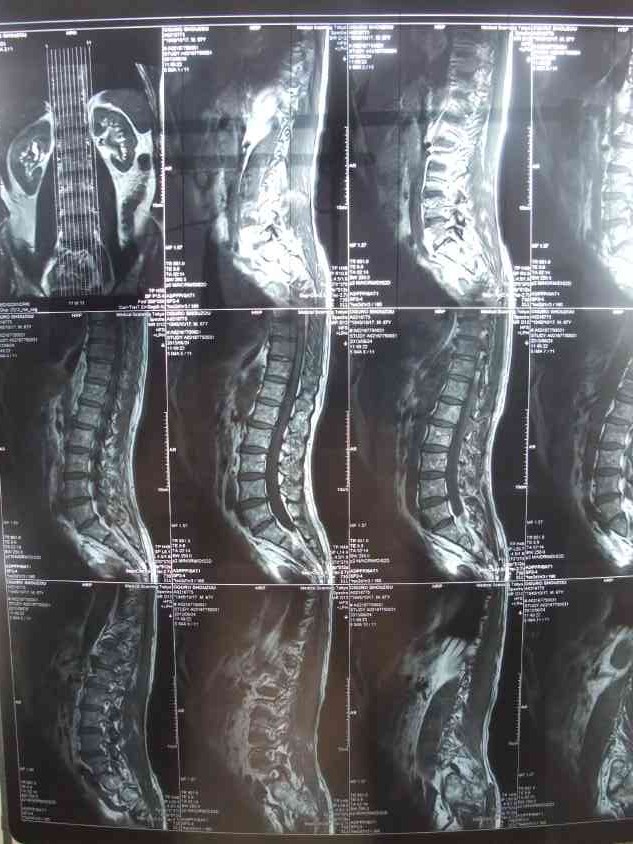

治まっていた腰痛が入梅頃から再発し、鍼灸院、マッサージ、カイロフラクティック等に通って治療していましたが、612日ギックリ腰とは違う激痛に見舞われ、日に日に痛さが増し少々歩行困難になってしまった。

新たに整形外科へも行きレントゲン検査をしたが「

624日にMRIの検査を」と言われ、

検査の結果は「椎間板に少し問題がありますが日常生活には問題ない」との事で

一安心しました。

(MRI撮影1/6)

結論付けるには速すぎますが、623日が激痛のピークだったようで、